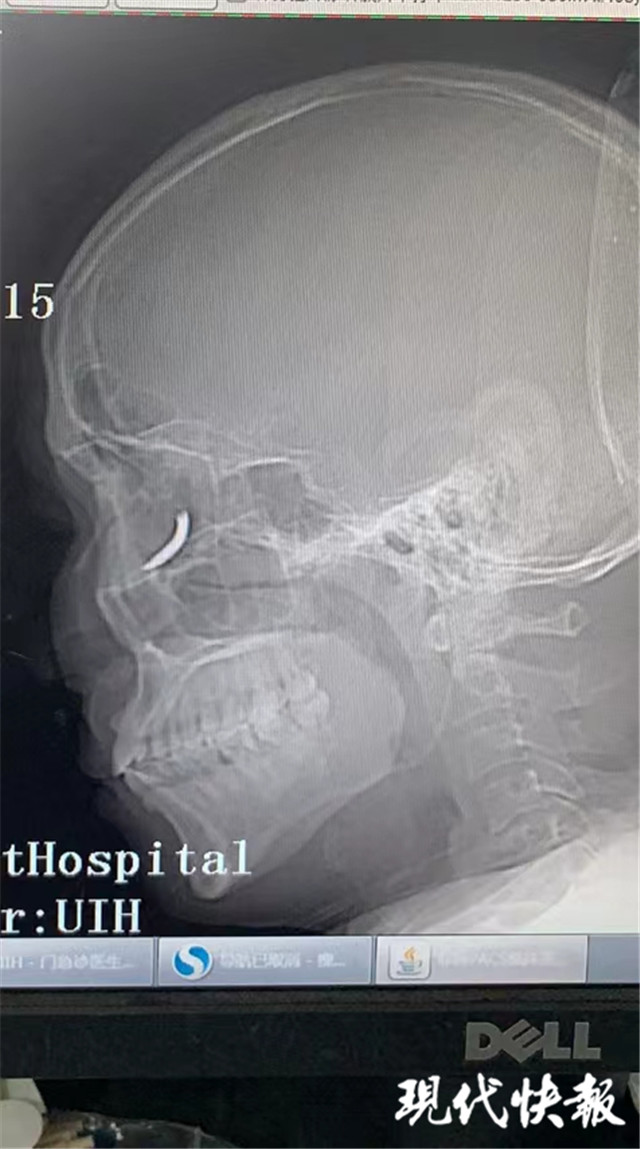

(通訊員 孫忠河 記者 梅書華)鐵釘扎入眼眶,卻不疼不癢,這是怎么回事?三天前,王師傅在溧水的建筑工地干活時,突然感覺有異物進(jìn)入眼內(nèi),但沒當(dāng)回事,后來出現(xiàn)頭暈才就診,沒想到是鐵釘扎入了眼眶。南京市第一醫(yī)院醫(yī)生通過半小時手術(shù),順利將一根長約一公分的鐵釘取出。

“當(dāng)時在敲鐵釘,感覺什么東西進(jìn)眼睛里了,但沒影響視力,還以為是水泥灰之類的。”三天前,王師傅眼中進(jìn)入異物,感覺頭暈不適后,去當(dāng)?shù)蒯t(yī)院就診,拍了X光片后,竟然發(fā)現(xiàn)自己眼眶內(nèi)有一個鐵釘樣的異物。

隨即,王師傅趕到南京市第一醫(yī)院眼科就診,眼科門診曹雪倩醫(yī)生接診后,立即完善CT等相關(guān)檢查。剛準(zhǔn)備休息的眼科醫(yī)生范偉杰,立即與副主任醫(yī)師趙貴陽聯(lián)合研究這個特殊的病例。專家們發(fā)現(xiàn)這枚鐵釘不偏不倚正好扎進(jìn)病人的眼眶里,但是眼眶內(nèi)解剖結(jié)構(gòu)復(fù)雜,要在盡可能保護(hù)正常組織結(jié)構(gòu)的情況下完成探查并取除鐵釘,手術(shù)難度較大。

范偉杰與趙貴陽反復(fù)討論后,制定了詳細(xì)周密的手術(shù)方案,最終以局麻下、眼袋美容切口進(jìn)入,順利取出了一根長約一公分的鐵釘。整臺手術(shù)耗時半小時,手術(shù)過程中沒有損傷到眼球壁和視神經(jīng),但醫(yī)生發(fā)現(xiàn)因為鐵釘?shù)那秩耄暰W(wǎng)膜周邊有出血,所以做了視網(wǎng)膜光凝。術(shù)后視力1.0,面部看不出瘢痕。王師傅的眼球終于安全保住了。